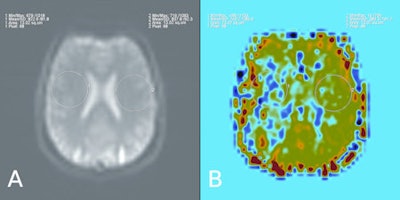

These six images show a comparison between contrast-enhanced perfusion and non-contrast perfusion using arterial spin labeling technique in a 34-year-old male with a chronic obliteration of the right middle cerebral artery. In the set of four contrast-enhanced perfusion images, A = time-to-peak (TTP), B = relative cerebral blood volume (CBV), C = relative mean transit time (MTT), D = relative cerebral blood flow (CBF). The other two are pulsed arterial spin labeling (QUIPPS II sequence) images. A: Sample of source data, signal in the circular region placed in the left hemisphere is 102% of that in the right. B: Relative cerebral blood flow, signal in the circular region placed in the left hemisphere is 271% of that in the right. Image courtesy of Dr. Josef Vymazal.ASL has found application in many research and clinical areas. One area that has received much attention is in the evaluation of patients with cerebrovascular disease, both in the initial assessment of perfusion as well as in evaluating treatment response. Vymazal believes the greatest limitation of these techniques may be that MRI is often not the preferred investigative method in acute situations. In non-emergency settings, however, ASL has the benefit of not only being a powerful, noninvasive perfusion imaging method, but also that it allows the investigative physician access to the many other high quality soft-tissue imaging techniques that can be applied in the MRI setting.